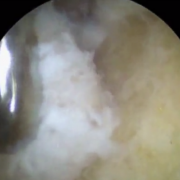

Initially portals (keyholes) are made on both sides of the patellar tendon a little proximal to (higher up from) the tibial tubercle. On one side I introduce an arthroscope, which has a light source, camera and fluid irrigation, and on the other side I introduce a motorised instrument which has a rotating shaver burr at its end.

Both of these instruments are passed into a natural space - or bursa - that exists under the tendon I burr away (debride) the excess prominent bone on the tibia, starting proximally and then continue distally (from top to bottom) until the patellar attachment is reached.

Then I turn my attention to the ossicle itself. I use a probe and then I shave it free from the softer tissues encasing it, and then I use a grasper to take it out. You can see the ossicle sandwiched between the ends of the grasper. It looks quite big but the camera magnifies it, and also there is soft tissue surrounding it.